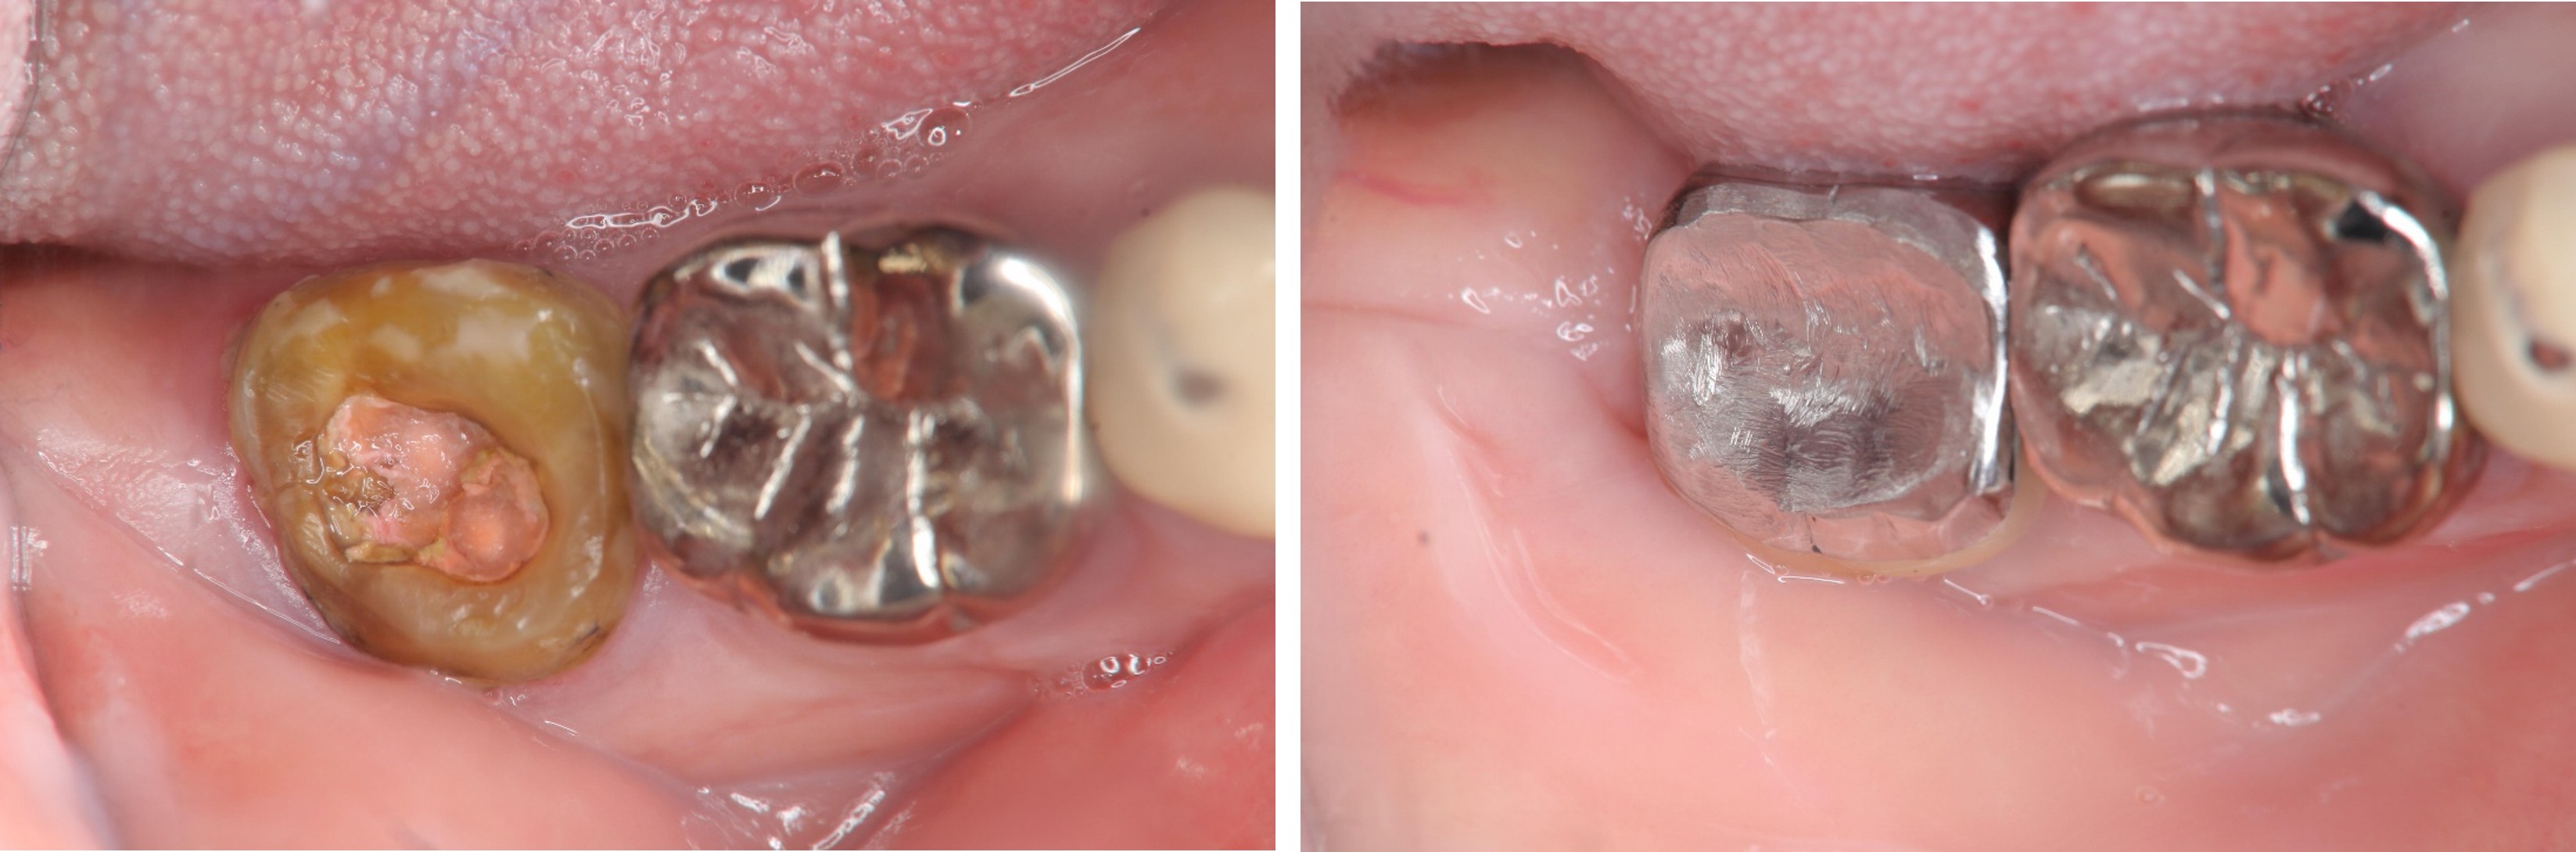

治療前,蛀牙齒質破壞

治療前,患者已接過根管治療

水雷射牙冠增長手術

術前、術後比較